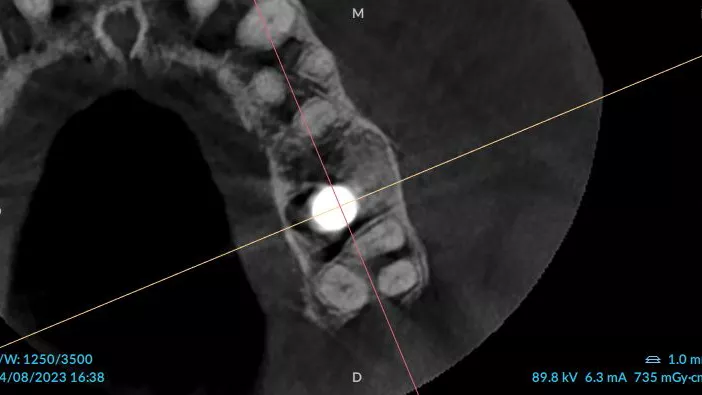

3a. 3b. 3c. 3D volumetric diagnosis and planning of implant therapy.

3a

3b

3c

10a. 10b. 10c. 3D scans and radiograph control of the implantplacement.

10a

10b

10c